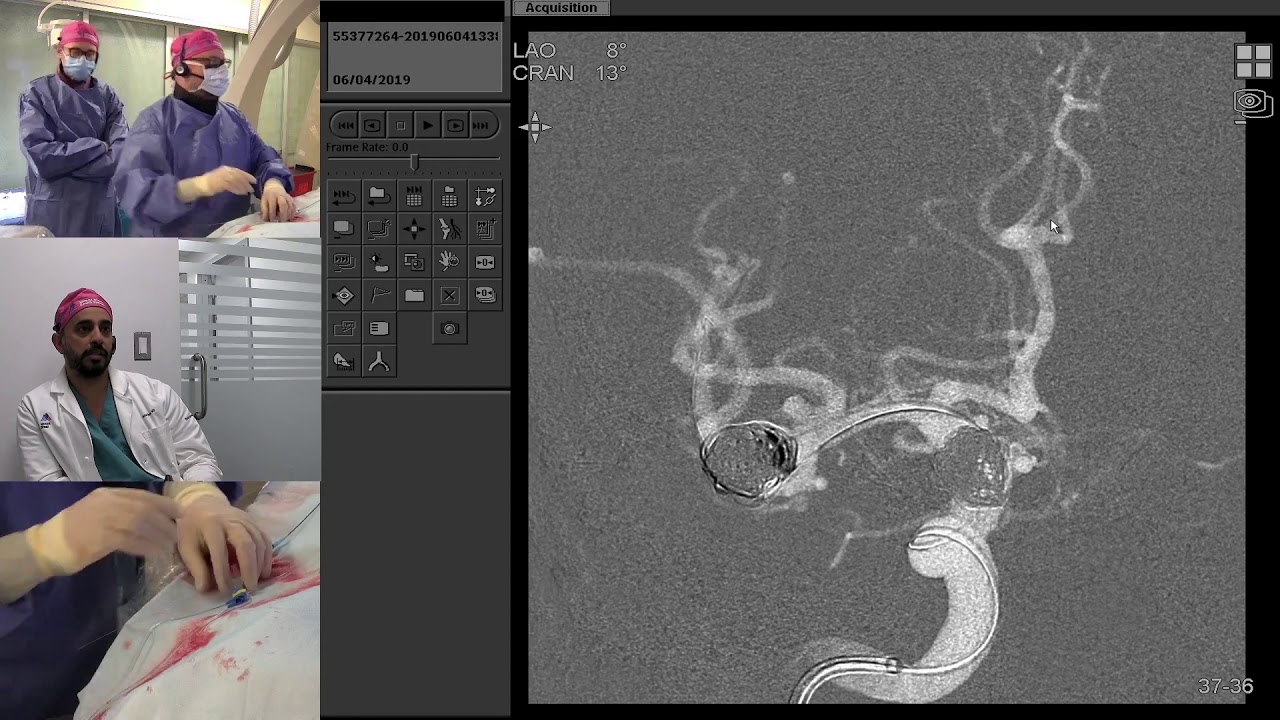

From www.youtube.com

Transradial Coil Embolization of Unruptured Intracranial MCA Bifurcation Aneurysm YouTube Coil Embolization Of Unruptured Intracranial Aneurysms Endovascular coil embolization is an option for treatment of ruptured and unruptured intracranial. Between january 2012 and december 2023, 435 patients with intracranial aneurysms (316 unruptured and 119 ruptured) underwent coil embolization at our hospital. Endovascular coil embolisation continues to evolve and remains a valid modality in managing ruptured and unruptured cerebral. Intraprocedural aneurysmal rupture is a feared complication of. Coil Embolization Of Unruptured Intracranial Aneurysms.